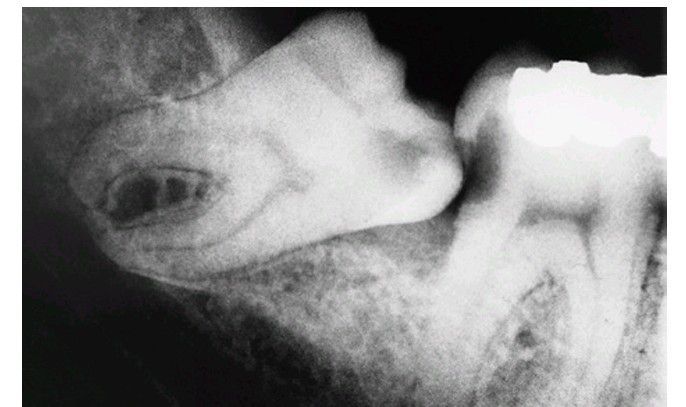

Sequela of an impacted 3rd molar

Radiograph of caries in an impacted third molar and a second molar.